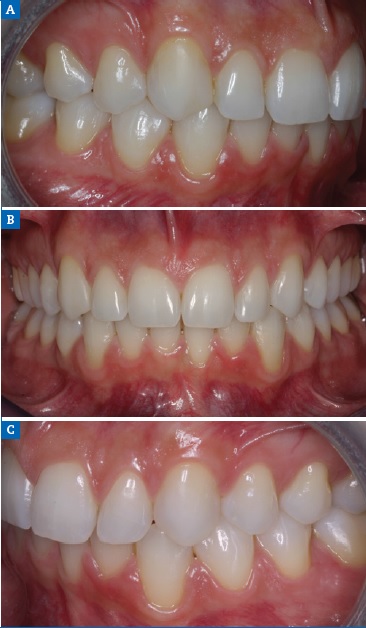

A 19-year-old female patient presented with primarily esthetic concerns. An intraoral examination revealed a Class I right molar, a Class II left molar, and a deep bite (Figure 17). Orthodontic treatment was performed to obtain bilateral Class I molar and canine relationship and, in turn, improve the overbite and remove the traumatic occlusion responsible for the gingival recession on the left mandibular incisor. Bolton’s anterior analysis confirmed a dental discrepancy in the anterior sector to mandibular excess with a proportion of 83.1% (13, 12, 11, 21, 22, 23 / 43, 42, 41, 31, 32, 33). It was caused by the maxillary dental microdontia and the need to carry out esthetic restorations in the upper arch. A space was created on the distal surface of both microdontic lateral incisors to establish the Bolton’s proportion17 (Figure 18). After orthodontic treatment, shade selection was accomplished using a Vita Shade Guide (Figure 19), and dental bleaching was performed to optimize the harmony of the smile.

Figure 18 Case 3: Intraoral views of the (A) right, (B) frontal, and (C) left aspects after the orthodontic treatment.

Then, to improve the morphology of the microdontic lateral incisors, a nanohybrid ORMOCER-based composite was applied. The right and left maxillary canines were also restored on the mesial face to enhance their anatomical shape (Figure 20A). This treatment plan made it possible to improve the Bolton discrepancy in the anterior mandibular excess relationship from a value of 83.1% to 79.6%. Diamond impregnated silicone polishers were used after occlusal adjustment (Figure 20B).

Cross-polarized photography revealed the monoshade resin color integration with natural teeth (Figure 20C). Intraorally, an optimal overbite and an overjet relationship were established, as was a good buccal occlusion with a Class I molar and canine. The gingival recession on the left mandibular central incisor was also improved. At the 3-year follow-up, the rehabilitation showed good soft-tissue adaptation and excellent esthetic maintenance (Figures 21).